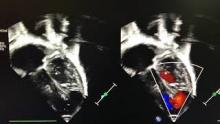

Lower ministernotomy was carried out and bypass was established with aortic and bicaval cannulation.The inferior vena cava cannula was inserted by a separate stab wound, which later became the drain exit. Cardioplegic arrest was achieved, the right atrium opened, and a vent sucker slid through the ASD. Both tricuspid and mitral valves looked normal. Attention was then turned to the apex, lifted with two tackle stitches. Interestingly, the anterior descending coronary artery was absent in its distal portion (a common finding in apical VSD). The apex was incised towards the boundaries of the VSD. A previously harvested glutaraldehide-treated autologous pericardial patch was parachuted to the muscular crescent with a running suture. On reaching both hinge points, the patch was further trimmed to size and sandwiched between the ventriculotomy edges. The ASD was partially closed, leaving a 3-4 mm residual pop-off and the atriotomy was closed. De-airing maneuvers and weaning off bypass on moderate inotropic support were performed as usual. Intraoperative echo showed good result.